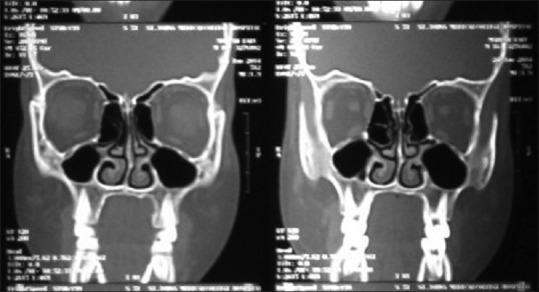

Mucoepidermoid carcinomas (MECs) of minor salivary gland origin are rare in children and adolescents and have been reported rarely. Literature regarding their clinical features and biologic behavior is scanty. The purpose of this case report is to discuss the clinical manifestation, diagnosis, and treatment plan of MEC of the palate. A 16-year-old male subject visited the Department of Periodontics, The Oxford Dental College and Hospital, Bangalore, India complaining of a painless swelling in the left posterior area of the hard palate since 6 months. Several clinical, radiographic, and histopathological investigations were carried out to rule out the lesion. Incisional biopsy of the lesion confirmed the diagnosis of lesion as MEC of the palate following which a wide surgical excision with adjacent free margins was carried out. This case report highlights the need for proper diagnosis and treatment plan in the cases of malignant tumors as it can lead to morbidity and mortality.

小唾液腺来源的黏液表皮样癌(MEC)在儿童和青少年中罕见,相关报道也很少。关于其临床特征和生物学行为的文献稀少。本病例报告的目的是探讨腭部MEC的临床表现、诊断和治疗方案。一名16岁男性患者前往印度班加罗尔牛津牙科学院及医院牙周病科就诊,主诉硬腭左侧后部无痛性肿胀已6个月。进行了多项临床、影像学和组织病理学检查以排除该病变。病变的切开活检确诊为腭部MEC,随后进行了广泛的手术切除并带有相邻的切缘。本病例报告强调了在恶性肿瘤病例中制定正确诊断和治疗方案的必要性,因为这可能导致发病和死亡。